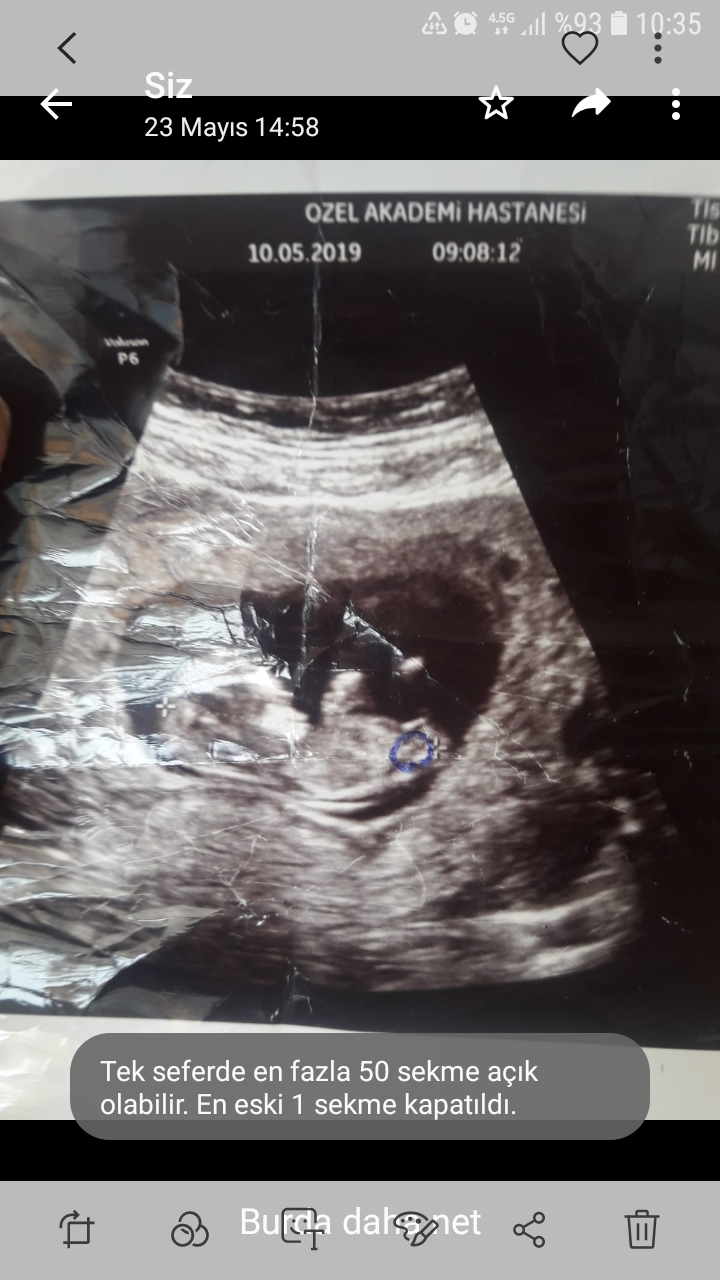

Merhabalar yüzde 80 seviyesinde ve daha yukarısı da diyebiliriz çocuğunuz kız görünüyor. Sevgiler iyi bayramlar dilerim...